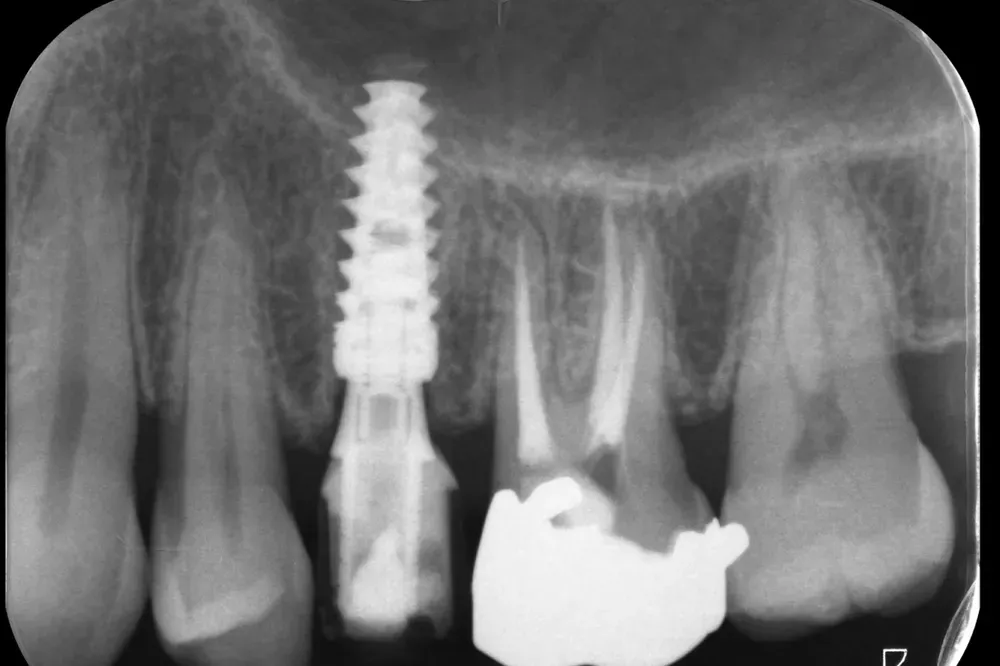

Impianto in Titanio di forma evoluta (Newton - Kalodon)

Le immagini radiografiche che seguono testimoniano alcune delle tante soluzioni tecniche che ho utilizzato per le arcate a carico immediato nel corso della mia carriera. Ogni caso presenta sfide diverse e richiede un approccio personalizzato.